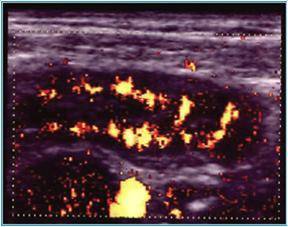

Compresia gradata sonografica este sugestiva pentru stabilirea cu acuratete a diagnsticului de apendicita. Apendicele apare ca o terminatie oarba, un fragment intestinal neperistaltic, cu originea la nivelul cecului. Printr-o compresiune maximala, se masoara diametrul antero-posterior al apendicelui. Testul este considerat pozitiv daca diametrul antero - posterior al apendicelui necomprimat este de 6 mm sau mai mult. Prezenta unui apendicolit stabileste diagnosticul. Imaginea ecografica a unui apendice normal, care este o structura tubulalara inchisa la un capat, usor compresibila, cu un diametru de 5 mm sau mai putin, exclude diagnosticul de apendicita acuta. Studiul este considerat negativ daca apendicele nu se vizualizeaza si nu exista o masa tumorala sau fluid pericecal. Cand se exclude ecografic diagnosticul de apendicita acuta, o scurta evaluare a restului cavitatii abdominale ar fi de preferat pentru stabilirea unui alt diagnostic. La femeile active sexual, organele pelvine genitale ar trebui vizualizate atat transabdominal, cat si transvaginal, pentru a exclude o patologie ginecologica care ar putea cauza durerea abdominala acuta.

Diagnosticul ecografic al apendicitei acute are o sensibilitate de 78 - 96 % si o specificitate de 85 - 98 %. Ecografia poate fi realizata in scop diagnostic la copii si femeile insarcinate, desi aplicabilitatea ei este oarecum limitata in ultimele luni de sarcina.

Ecografia are o serie de limite nete si rezultatele sunt dependente de experienta celui care o efectueaza. O imagine fals pozitiva poate sa apara in prezenta unui proces inflamator periapendicular determinat de inflamatia tesuturilor limitrofe; o dilatare a trompelor uterine poate fi confundata cu o inflamatie apendiculara, resturi de fecale neevacuate pot mima un apendicolit, iar la pacientii obezi, apendicele poate fi incompresibil atat datorita procesului inflamator acut, dar si datorita stratului de tesut adipos. Ecografii fals negative pot sa apara in conditiile unei limitari a procesului inflamator la varful apendicelui, in apendici cu localizare retrocecala, atunci cand este marit si poate fi confundat cu intestinul subtire sau in caz de perforatie apendiculara cand este comprimat.

Fig. 11 Apendicita acuta cu hiperemie parietala